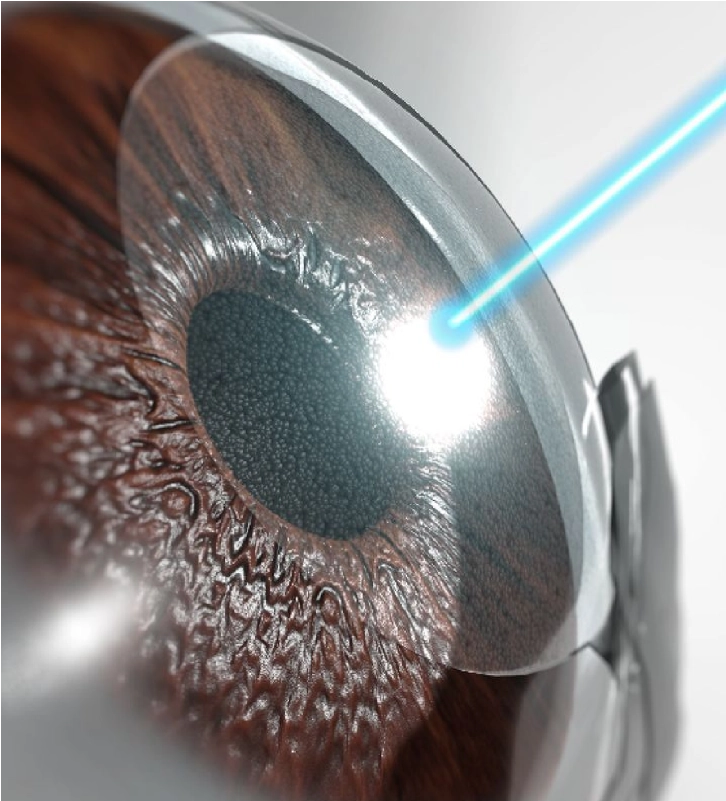

CIRUGÍA LASIK / FEMTOLASIK

LASIK / Femto-LASIK

¡Mejora tu visión! Reduce o elimina la dependencia de anteojos. Sin estadía.